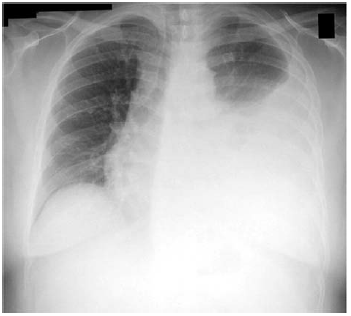

No que concerne a esse caso clínico hipotético, e considerando a imagem radiográfica apresentada, assinale a alternativa que indica, respectivamente, a hipótese diagnóstica e o tratamento para esse paciente.

Provas

Com base nesse caso clínico hipotético e na imagem radiográfica apresentada, e considerando os conhecimentos médicos correlatos, assinale a alternativa correta.